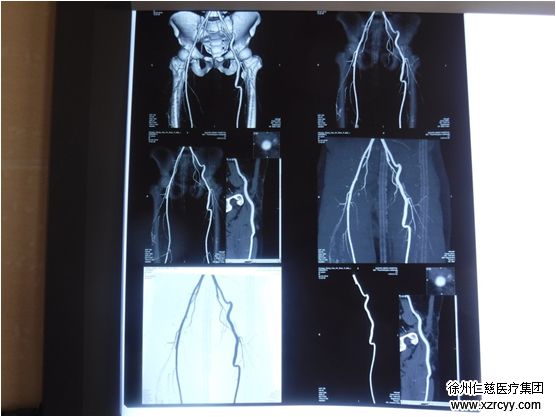

入院检查CTA

“你看这份入院时的CTA检查,盆骨血管损伤(左髂外动静脉、股动静脉),左下肢筋骨模式综合征,腹部、下背等多处肌肉肌腱损伤。”betway在线登陆手外科李明医生介绍,以前血管缺损是移植自体其他部位血管来代替,但是这次患者堵的是主动脉,没有那么粗的自体血管替代。经过医院手足显微外科多位专家对患者病情进行评估,为其量身制定了人工血管移植修复长段栓塞髂外动脉手术方案,一段直径相仿、长度适中的人工血替换损伤血管,重建血循环。

术后18天CTA检查恢复良好